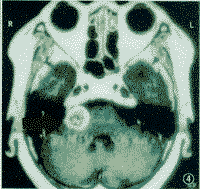

4.放射學檢查(1)顱骨X線片:岩骨平片見內耳道擴大、骨侵蝕或骨質吸收。(2)CT及MRI掃描:CT表現為瘤體呈等密度或低密度,少數呈高密度影像。腫瘤多為圓形或不規則形,位於內聽道口區,增強效應明顯。MRIT1加權像上呈略低或等信號,在T2加權像上呈高信號。第四腦室受壓變形,腦幹及小腦亦變形移位。注射造影劑後瘤實質部分明顯均一強化,囊變區不強化。

(3)CT及MRI檢查:目前聽神經鞘瘤診斷的標準是Gd-DTDA增強的MRI,特別是當腫瘤很小(<1cm)或在內聽道內,CT掃描陰性又高度懷疑腫瘤存在時應該進行GD-DTPA增強的MRI。CT與MRI兩種檢查有相輔相成的作用,如CT發現有病側內聽道擴大時,增強CT可發現腫瘤對於估計中顱窩入路時顳骨的氣化程度及高頸靜脈球與後半規管及底的距離有幫助。如果病人已作了CT而腫瘤較大,MRI可提供對腦幹壓迫的範圍Ⅳ腦室是否通暢腦積水、是否存在的情況對可疑聽神經鞘瘤或CT檢查難於確定時,全序列的MRI可做出鑑別診斷。但也要注意Gd-DTPA的可能假陽性,這與內聽道內神經的炎症或蛛網膜炎有關;任何小的接近底部的增強病變應該在六月後作MRI複查,以評估其生長情況。